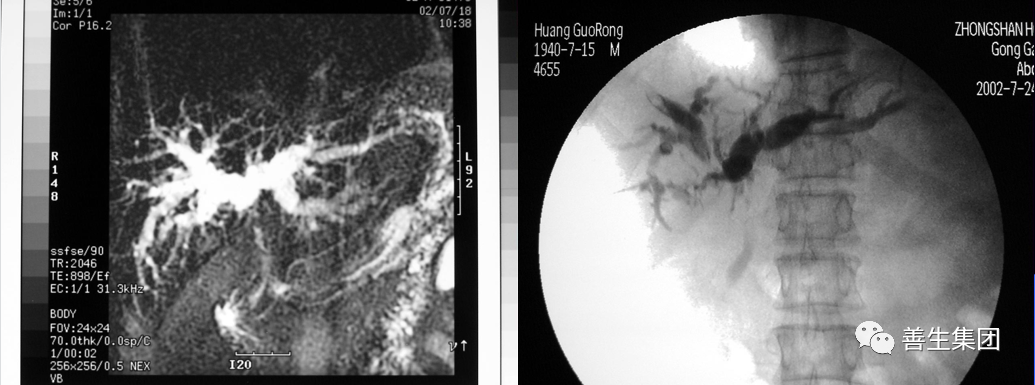

PTC示左右肝管内间广泛充盈缺损,为胆道出血正像

胆管支架什么样子经皮肝胆管穿刺置管引流术(PTCD)及胆道内支架临床应用_https://www.jmylbn.com_新闻资讯_第5张

胆管支架什么样子经皮肝胆管穿刺置管引流术(PTCD)及胆道内支架临床应用_https://www.jmylbn.com_新闻资讯_第6张